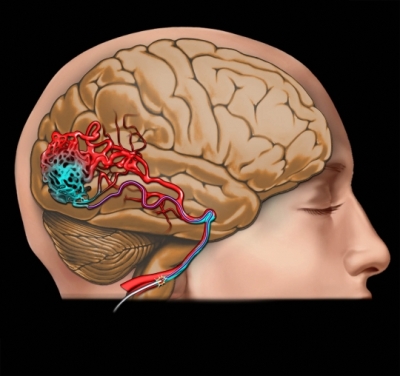

Embolización de la arteria meníngea media en el hematoma subdural subagudo o crónico

21 noviembre 2024

Tres ensayos clínicos exploran la utilidad de la embolización de esta arteria en el manejo del hematoma subdural subagudo o crónico, con miras a reducir la tasa de recurrencias y la necesidad de nuevas intervenciones. New England Journal of Medicine, 20 de noviembre de 2024.